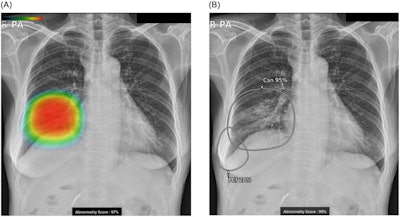

Lunit's Insight CXR was approved in Korea in 2018. The software indicates the location of lesions suspicious for major lung abnormalities, such as nodules, consolidation, and pneumothorax.